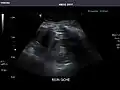

Liver

Ultrasonography of the liver with some standard measurements[6]

In patients with deranged liver function tests, ultrasound may show increased liver size (hepatomegaly), increased reflectiveness (which might, for example, indicate cholestasis), gallbladder or bile duct diseases, or a tumor in the liver.